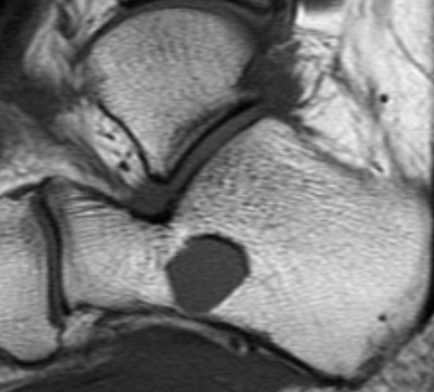

IRM

- Signal Kystique HyperT2 HypoT1

- Possible niveau si hémorragie

Localisation Calcanéenne Typique